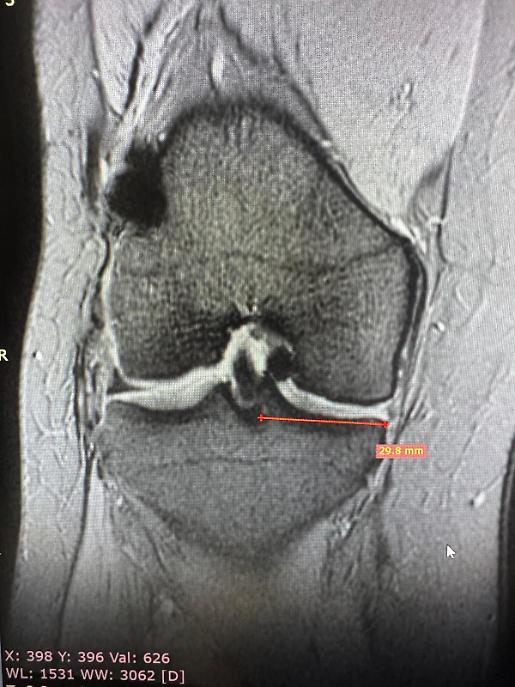

Nel caso specifico, è stato impiantato un menisco proveniente da donatore senza l’utilizzo di componenti ossee. La stabilizzazione è stata ottenuta attraverso suture capsulo meniscali e radiali, una tecnica che consente un ancoraggio solido e una corretta integrazione del tessuto trapiantato.